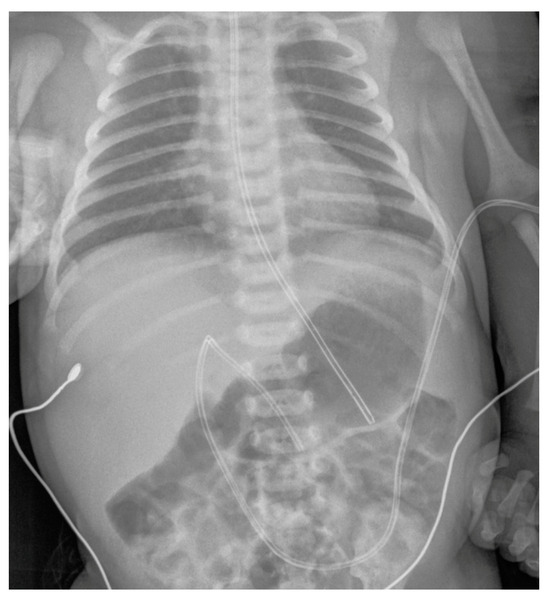

Conventional Radiology Evaluation of Neonatal Intravascular Devices (NIVDs): A Case Series

3. Results